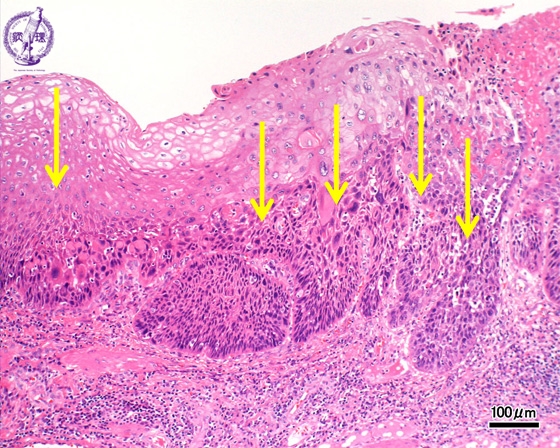

- ★(3)Esophageal carcinoma (squamous cell carcinoma)

Microscopic view (H&E stain, intermediate power): The basilar epithelium is occupied by atypical cells which show expansive invasion into the lamina propria (squamous cell carcinoma, arrow).